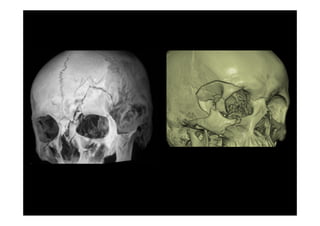

Fracturas complejas de la cara

Fracturas del Complejo Naso-

Etmoido-Maxilo-Fronto-Orbitario

Fracturas complejes de la cara

Fracturas Cigomáticas Complejas

Fracturas Órbito-craneanas